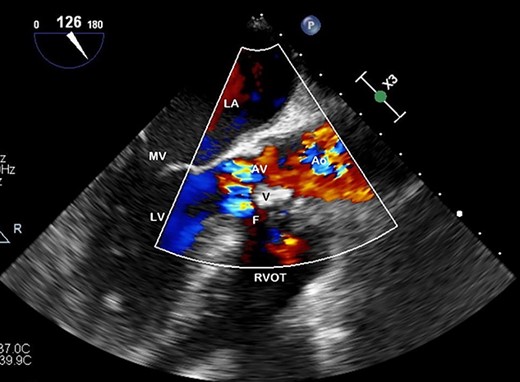

TOE, long axis demonstrating a vegetation (V) on the AV obstructing the left ventricular outflow tract; Ao, aorta; F, fistula; LV, left ventricle; MV, mitral valve.

Preoperative TOE, long axis with colour flow highlighting the vegetation (V) obstructing flow through the AV and the fistula (F) which has developed from left ventricular outflow tract to RVOT.